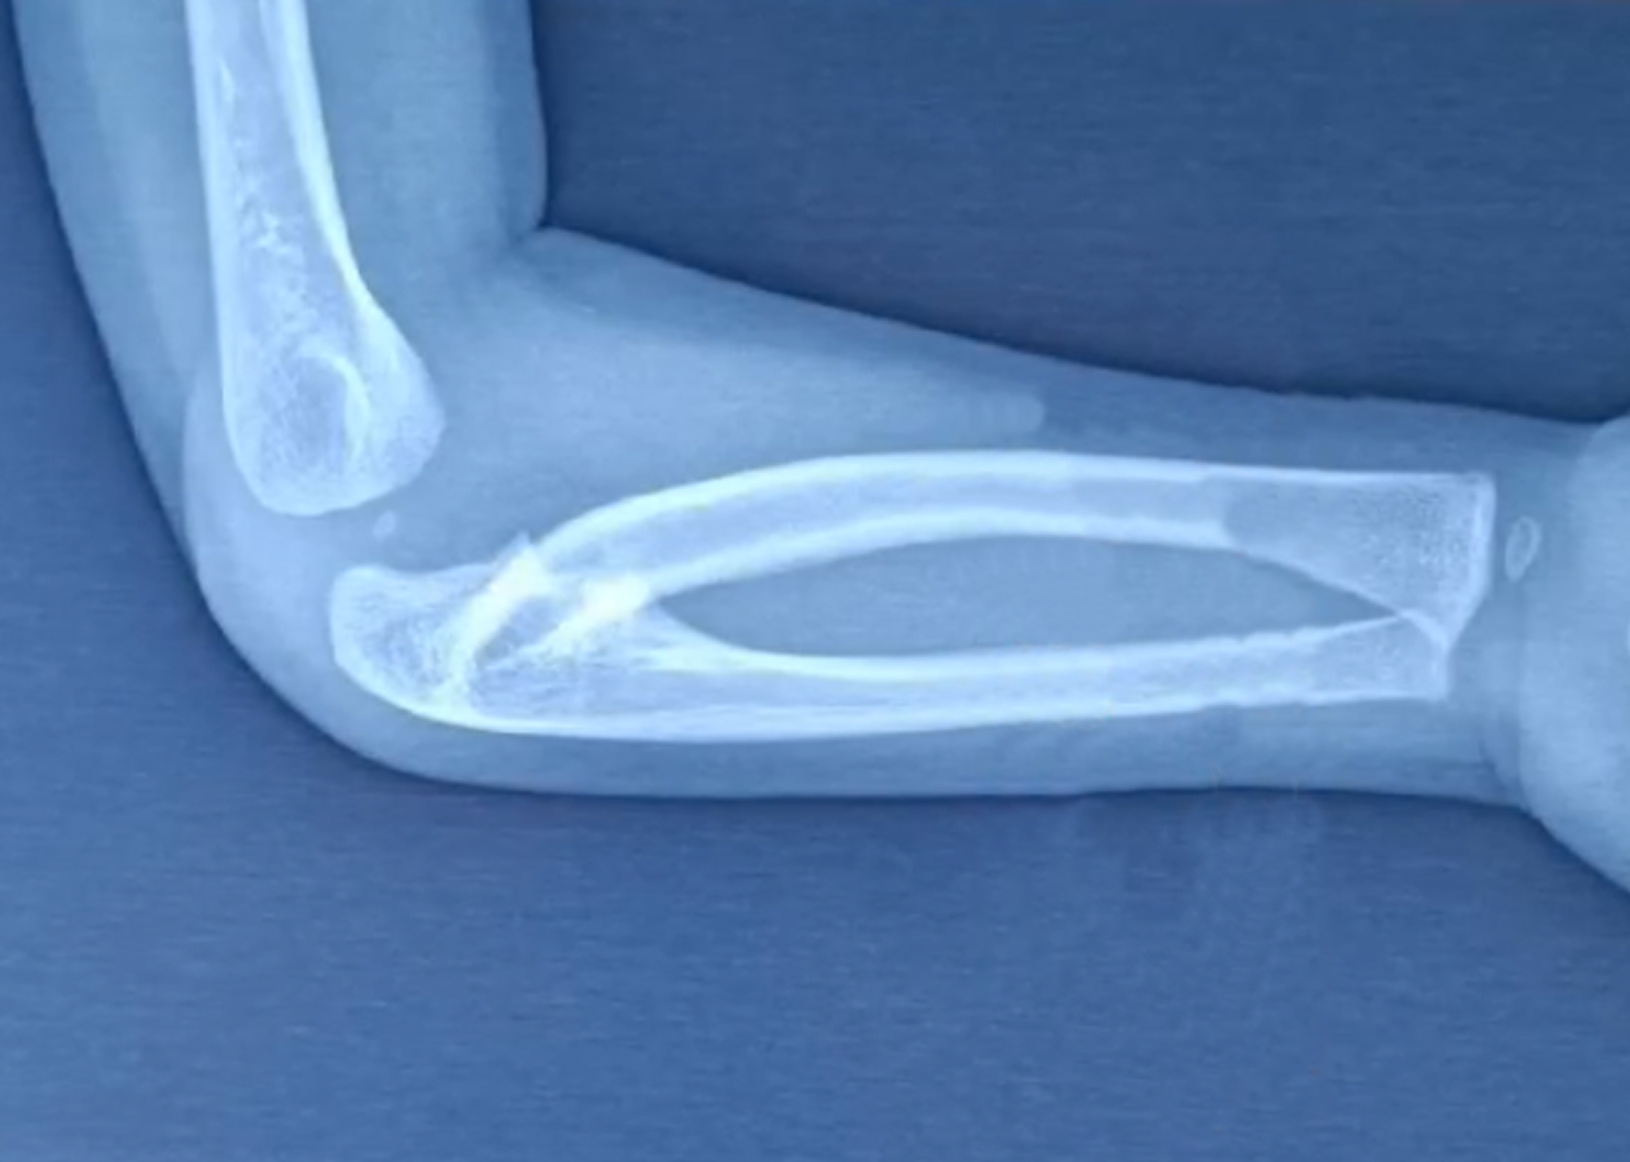

宝贝天生手掌不能朝上,微创手术后终于可以如愿以啦!

上尺桡关节融合